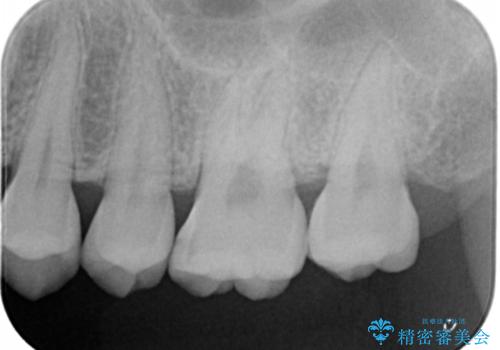

- 歯が黒くなってきているのが気になるとのことで、レントゲンを撮影し診断を行いました。

幸い神経までは到達していない虫歯だったため、部分的な詰め物「インレー」で治療を行うこととなりました。